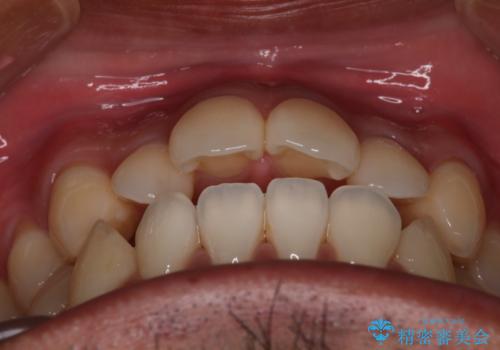

【審美装置】開口(オープンバイト)を改善

- 全体的に歯並びをよくしたいとのことで来院されました。初診時、患者様はセラミック矯正とワイヤー矯正で迷われていました。

開口(オープンバイト)のため噛み合わせを考慮してワイヤー矯正を提案させていただきました。

IPR(歯と歯の間を削る処置)と顎間ゴムを行い歯並びを整える治療計画を立てました。